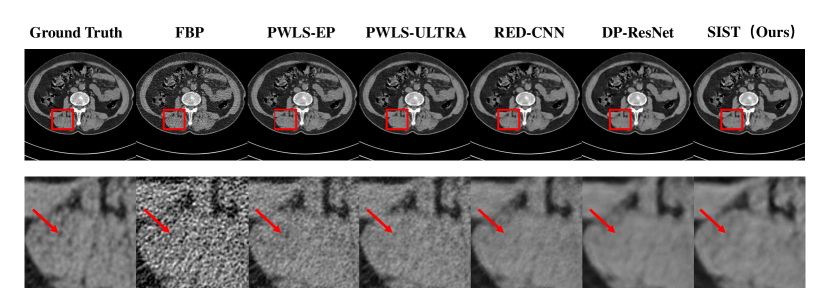

Refer to caption

Figure 5: Visual results in LDCT Dataset. The first and third rows are denoised images. The second and fourth rows are zoomed regions in red boxes. All images displayed are from the same window of [-460, 540].

4.3.1 LDCT Dataset

We first conduct the experiments on the Low-Dose CT Image and Projection Dataset. Tab.1 gives quantitative results of all methods. Note that FBP in Tab.1 are images directly reconstructed from a low-dose sinogram using FBP. From these results, we can observe that deep learning methods outperform iterative reconstruction methods thanks to the delicate designed CNN architectures. By further utilizing the sinogram inner-structure information, our method achieves the best performance in all three metrics. Visual results are shown in Fig.5. It can be observed that our proposed method outperforms others.